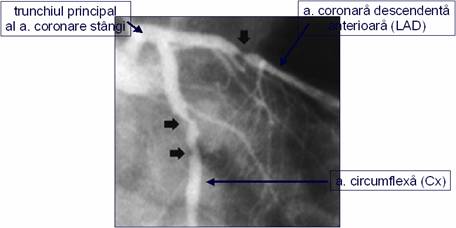

Aspect angiografic de "left

main"

Aspect angiografic

"left main" echivalent